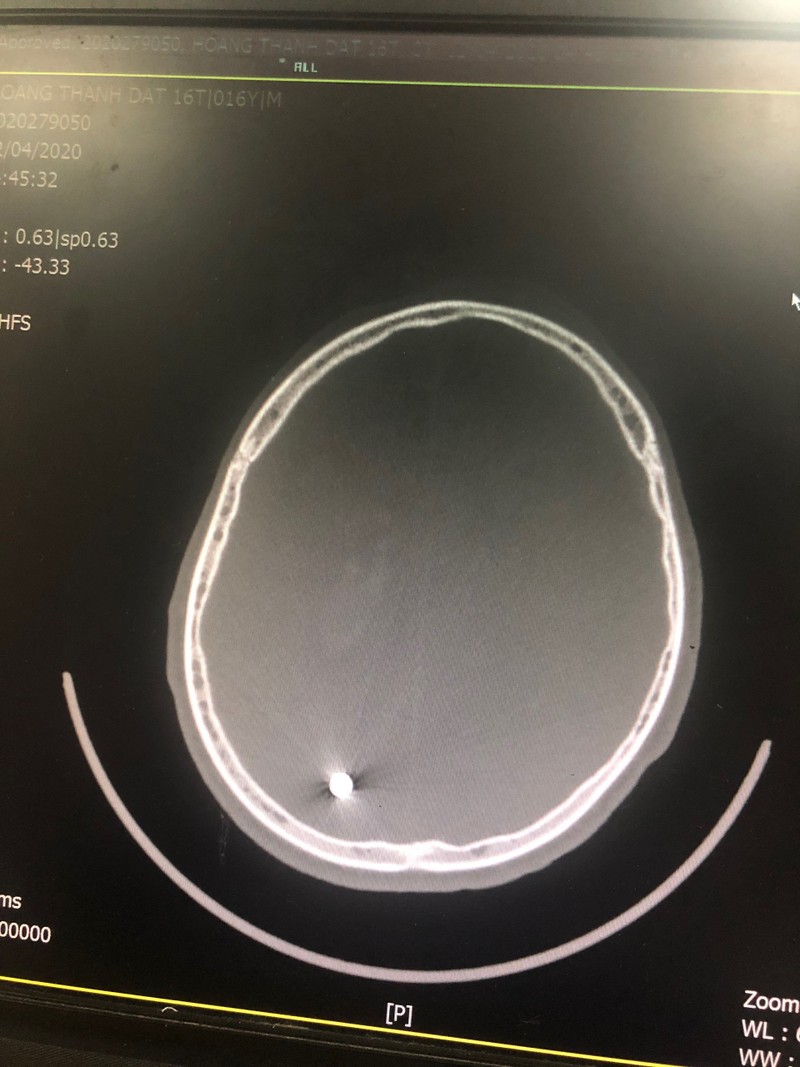

Tại Bệnh viện Hữu nghị Việt Đức, các bác sĩ đã tiến hành cấp cứu kịp thời cho người bệnh, Kết quả chụp X-quang phát hiện vết thương nhỏ đường kính 0,55mm xuyên qua não từ trán đến đỉnh chẩm bên phải. Vết thương xuyên dọc theo chiều dài não đã khiến em Đ. bị liệt nửa người bên trái.

Phim chụp vết thương viên đạn xuyên qua não của bệnh nhân Đ. Ảnh: BVCC |

Các bác sĩ đã tiến hành phẫu thuật lấy viên đạn trong não cho bệnh nhân. Sau mổ, bệnh nhân Đ. tỉnh táo, vẫn bị liệt nửa người do thương tổn não.